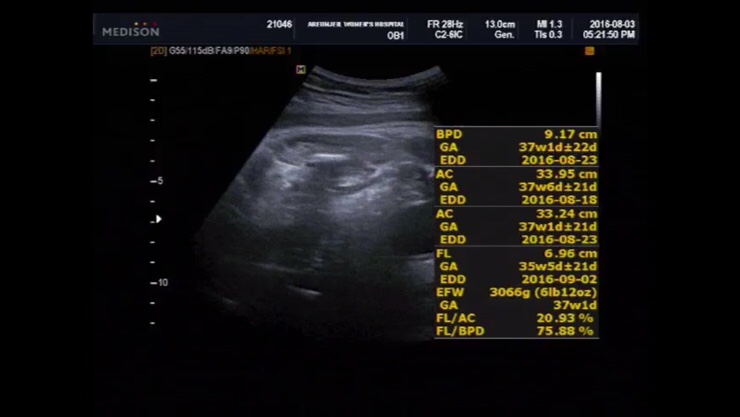

임신 39주 2일 검진 및 두번째 내진

임신 39주 2일 증상, 두번째 내진 끝없는 가진통과 이슬 새로운...